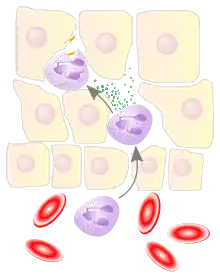

Phagocytosis

Extravasated neutrophils in the cellular phase come into contact with microbes at the inflamed tissue. Phagocytes express cell-surface endocytic pattern recognition receptors (PRRs) that have affinity and efficacy against non-specific microbe-associated molecular patterns (PAMPs). Most PAMPs that bind to endocytic PRRs and initiate phagocytosis are cell wall components, including complex carbohydrates such as mannans and β-glucans, lipopolysaccharides (LPS), peptidoglycans, and surface proteins. Endocytic PRRs on phagocytes reflect these molecular patterns, with C-type lectin receptors binding to mannans and β-glucans, and scavenger receptors binding to LPS.

Upon endocytic PRR binding, actin-myosin cytoskeletal rearrangement adjacent to the plasma membrane occurs in a way that endocytoses the plasma membrane containing the PRR-PAMP complex, and the microbe. Phosphatidylinositol and Vps34-Vps15-Beclin1 signalling pathways have been implicated to traffic the endocytosed phagosome to intracellular lysosomes, where fusion of the phagosome and the lysosome produces a phagolysosome. The reactive oxygen species, superoxides and hypochlorite bleach within the phagolysosomes then kill microbes inside the phagocyte.

Phagocytic efficacy can be enhanced by opsonization. Plasma derived complement C3b and antibodies that exude into the inflamed tissue during the vascular phase bind to and coat the microbial antigens. As well as endocytic PRRs, phagocytes also express opsonin receptors Fc receptor and complement receptor 1 (CR1), which bind to antibodies and C3b, respectively. The co-stimulation of endocytic PRR and opsonin receptor increases the efficacy of the phagocytic process, enhancing the lysosomal elimination of the infective agent.